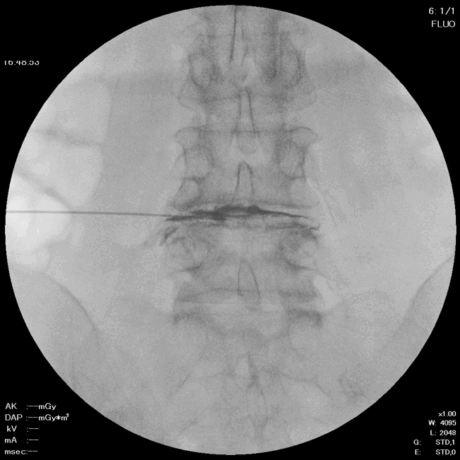

椎間板造影と同じように椎間板に穿刺し、局所麻酔を行います。

頚椎では前方から、腰椎では後方から、神経を圧迫している部位にアプローチします。

2. ニードル留置

直径約2mmのニードルを椎間板に留置します。